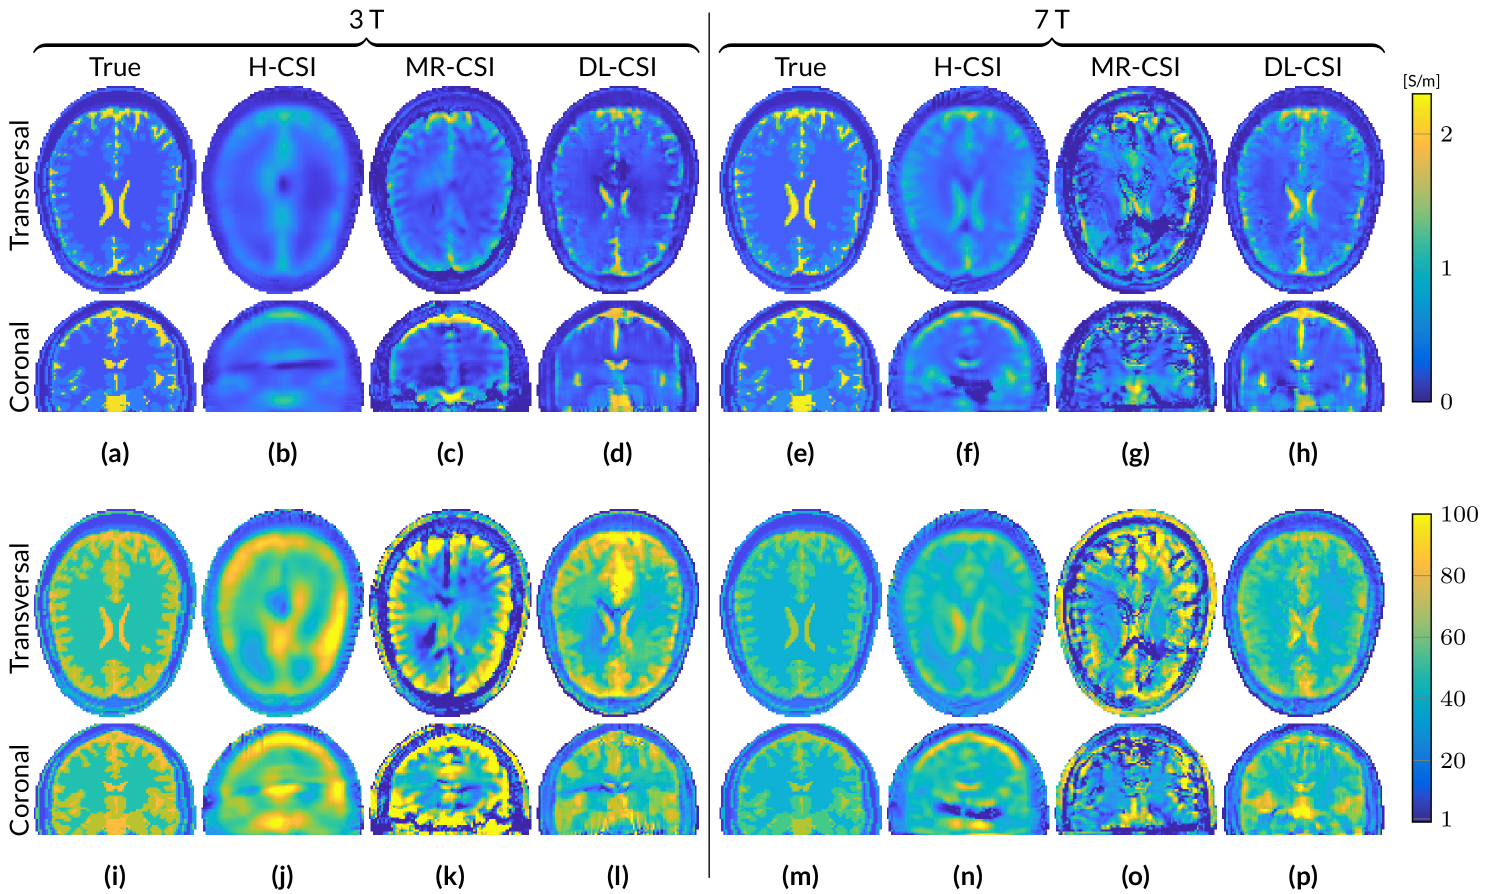

Figure 3: Absolute error maps (ground truth - reconstruction) of the reconstructions from the different EPT approaches, for the Duke head model at 3 T and 7 T. The values in the subcaptions denote the RRE of the whole volume. Conductivity (a-j) and permittivity (k-t).

Figure 3 gives a qualitative impression of the reconstruction errors of the five different reconstruction methods, by showing the absolute error maps for EP reconstructions from noisy B^1+superscriptsubscript^𝐵1\hat{B}_{1}^{+} data. For a direct quantitative comparison, the computed RRE in the whole domain is also reported in the figure for each reconstruction method.

MR-EPT reconstructions show severe errors due to noise amplification in the reconstructed EP maps at 3 T. These errors are reduced for 7 T MR-EPT reconstructions. However, the quality of the reconstructed EP maps remains still poor. DL-EPT reconstructions, available only at 3 T, show good accuracy in homogeneous regions. However, reconstruction errors are present at tissue boundaries, e.g. around the ventricles. H-CSI shows substantial errors arising from the low |𝑬^|^𝑬|\hat{\bm{E}}|-field region. These errors appear as artificial bands/shadow artifacts, which are intrinsically caused by the homogeneous initialization. MR-CSI is strongly affected by the reconstruction errors present in MR-EPT, which is used as initialization guess. Although the RRE is lower compared to MR-EPT reconstructions, the quality of MR-CSI is still poor. DL-CSI reconstructions show good quality EP maps. The combined conductivity and permittivity RRE values of DL-CSI are lower compared to H-CSI both at 3 T and 7 T, showing an advantage in using DL as initialization guess. Artifacts such as artificial bands present in H-CSI reconstructions are highly reduced in DL-CSI. Improvements are also observed with respect to DL-EPT (see Figure S1), especially for conductivity reconstructions around the ventricles.